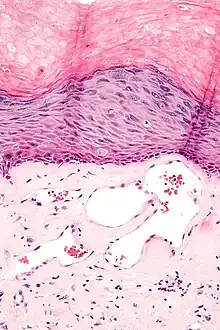

Angiokeratomas characteristically have large dilated blood vessels in the superficial dermis and hyperkeratosis (overlying the dilated vessels).

Scrotal angiokeratoma (Fordyce type); dilated cavernous capillaries, acanthosis